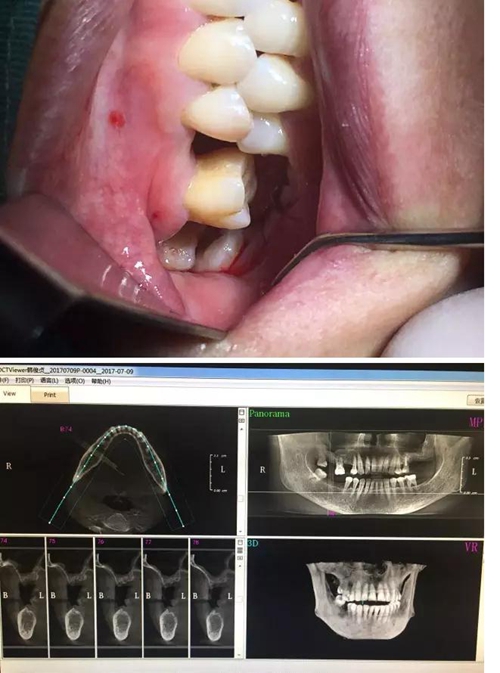

【病例分享】內(nèi)提,用自體骨柱,不用骨粉

2.jpg